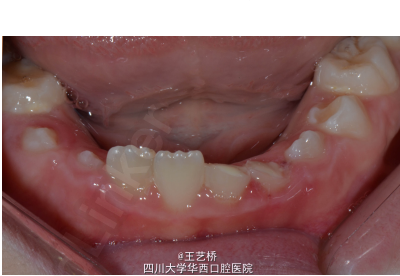

患儿一天前外伤导致下前牙缺损,患牙,无疼痛或者不适,牙碎片保存在密闭的自来水溶液中。

检查发现31、32牙牙体缺损,牙本质暴露,未暴露牙髓,牙周组织健康,叩诊(-),牙髓活力正常。断面覆盖玻璃离子水门汀临时修复材料。X线片31、32牙根尖周未见明显异常。